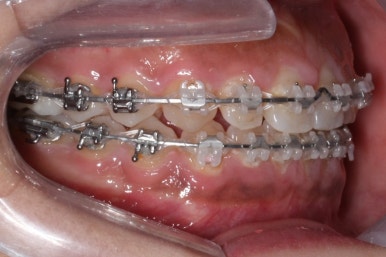

장치 부착 모습입니다.

이번에 부산치아교정치과에서 사용한 장치는 클리피씨라는 자가결찰 세라믹입니다.

철사를 잡아주는 캡이 장치에 달려 있어서 사용도 간편하고 치료시간도 짧아집니다.

바로 미니스크류 입니다. 위 사진에서 화살표 부분이 바로 미니스크류 입니다.

뼈에 단단히 고정해 놓고 어금니를 앞으로 당겨오는데 사용을 하게 됩니다. 교정치료 후에는 제거하게 되며 긍방 뼈가 차기 때문에 별로 걱정은 하지 않으셔도 됩니다.